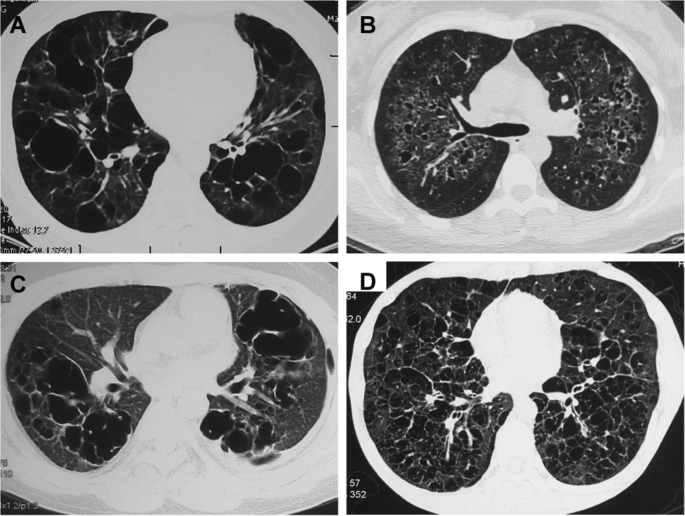

Cysts were bilateral in all patients. Lower lung-predominant cysts were more likely to be found in patients with BHD syndrome (58% of patients) (Fig. 1) than in patients in the LAM (no patients, p < 0.001) (Fig. 2) or the NBNL group (26% of patients, p = 0.020). Significant difference was also found in the axial distribution of pulmonary cysts. All cysts were diffuse in the non-BHD group, and 18 of 33 patients (55%) in the BHD group had cysts predominance near the mediastinum (p < 0.001).

The morphology of the pulmonary cysts was variable within individual patients. The appearance of fusiform cysts was observed in 27 patients in the BHD group (82%), while only 5 cases had fusiform cysts in the LAM group (15%, p < 0.001) and 5 patients in the NBNL group (22%, p < 0.001).

In terms of the number of cysts, 58% of patients in the BHD group had fewer than 50 lung cysts, while all patients in the LAM group (p < 0.001) and 78% patients in the NBNL group had more than 50 lung cysts (p = 0.008).

The distribution of the largest cysts was different. The largest cyst was located in the lower lobe in 28 patients (85%) in the BHD group, while 11 of 33 patients (33%) in the LAM group and 10 patients (43%) in the NBNL group had the largest cyst in the lower lobe. When comparing the diameters of the largest cysts between patients in two groups, the median diameters were 45 mm in the BHD group and 16.5 mm in the LAM group. Significant differences in the distribution of the diameter of the largest cysts were noted between the BHD and LAM groups (p < 0.001) and the NBNL group (p = 0.001) (Table 2 and Fig. 3).